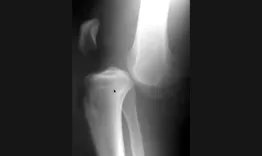

The objective of this course with Etienne Cavaignac is to learn how to diagnose osteochondritis dissecans and to explore the different therapeutic options, both in pediatric and adult patients.